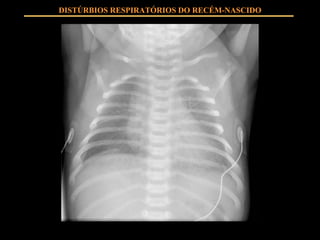

FISIOPATOLOGIA Insuficiente SURFACTANTE produzido por pneumócitos II Instabilidade alveolar com tendência ao colapso em expiração Extravasamento de líquido ao alvéolo Hipoventilação alveolar Shunts intrapulmonares Hipoxemia, hipercapnia DISTÚRBIOS RESPIRATÓRIOS DO RECÉM-NASCIDO

QUADRO CLÍNICO Estigmas de prematuridade Taquipnéia Esforço respiratório Cianose Hipoventilação DISTÚRBIOS RESPIRATÓRIOS DO RECÉM-NASCIDO